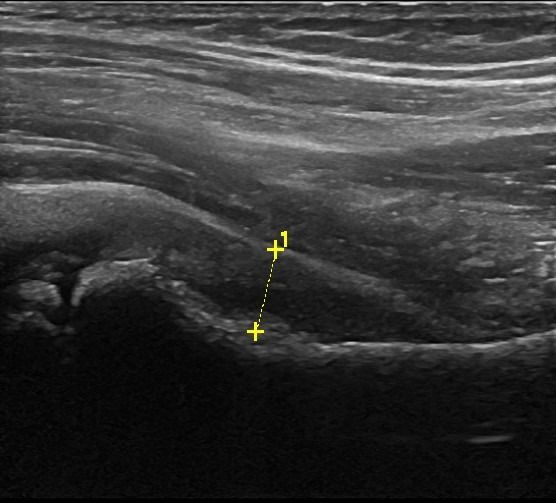

- Συλλογή υγρού

- Τροχαντηρίτιδα: συλλογή υγρού στους θυλάκους των γλουτιαίων τενόντων στο μείζονα τροχαντήρα

- Θυλακίτιδα: Συλλογή υγρού στο θύλακο του τένοντα του Λαγονοψοΐτη